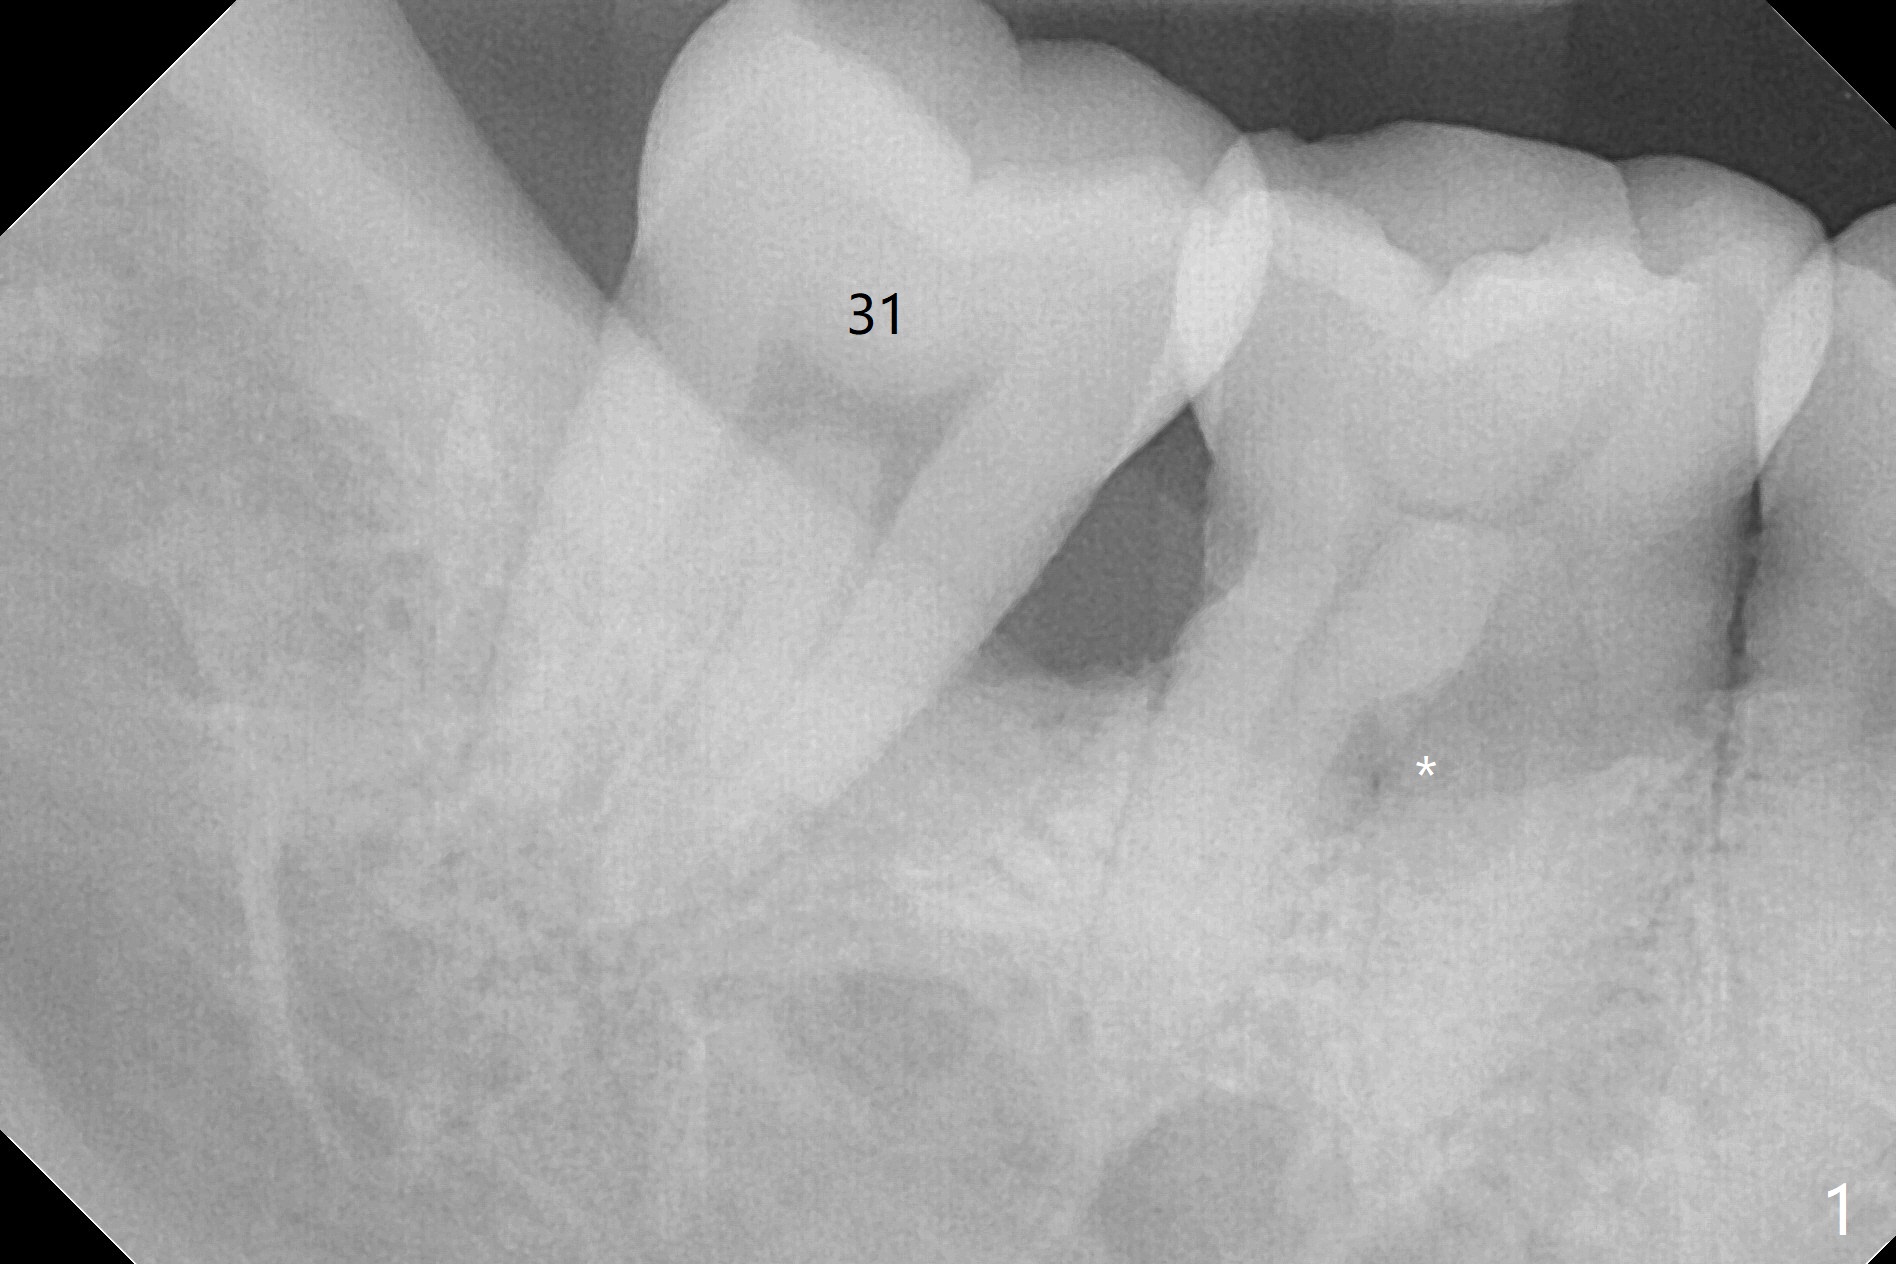

A 53-year-old man requests extraction of #30 and 31 post-SRP (Fig.1 (*: furca radiolucency). There is severe hemorrhage from the sockets post extraction, which makes bone graft difficult (Fig.2). Osteogen plug should have been used in stead of Ossogen. The socket openings are closed with 12x12 and 8x8 mm BioXclude and 4-0 PGA. The root curvature of the tooth #29 (Fig.2 *) suggests bruxism. The sockets heal 12 days postop (Fig.3). The septum at #30 (Fig.1 *) remains 6 months postop. Be wary of deviation off the septum during osteotomy. Bone density at #30 and 31 is high (1400-1700 units, Fig.5,6). Be careful of bone heat during osteotomy. It appears that cortical taps are pending.